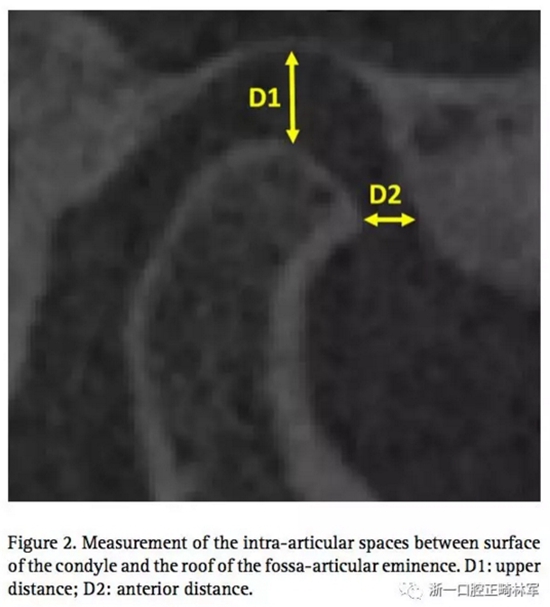

通過(guò)這個(gè)正常TMJ關(guān)節(jié),設(shè)計(jì)其他三個(gè)模型,包括有無(wú)??墊的,有無(wú)關(guān)節(jié)盤前移位的。因此,志愿者需要佩戴??墊進(jìn)行CT掃描,去分析上頜距離D1和關(guān)節(jié)間隙(關(guān)節(jié)面和關(guān)節(jié)窩之間)上部分距離D1和前部分距離D2。(圖2)可以發(fā)現(xiàn),因?yàn)槟パ篱g2mm的??墊,前關(guān)節(jié)腔有少量的增長(zhǎng),還有髁突輕微的旋轉(zhuǎn)。